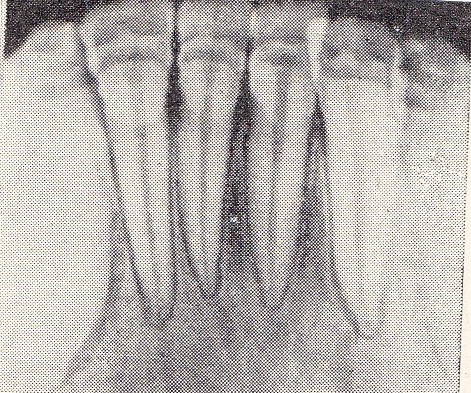

| Рис. 3. Остеопороз костной ткани в середине межальвеолярных перегородок. У верхушек корней видны интерсептальные щели. Высота межзубных перегородок на уровне эмалево-цементной границы. Рис. 4. Остеопороз межзубных перегородок. Рисунок губчатого вещества межальвеолярной перегородки виден только в области верхушек корней. Кортикальные пластинки вершин и боковых отделов межзубных перегородок выражены отчетливо. Высота межзубных перегородок на уровне эмалево-цементной границы. Рис. 5. Небольшой очаг остеопороза в среднем отделе межзубной перегородки, расположенной между 31 и 41. Рис. 6. Остеопороз губчатого вещества межзубных перегородок, вершины их на уровне эмалево-цементной границы нечеткие. |